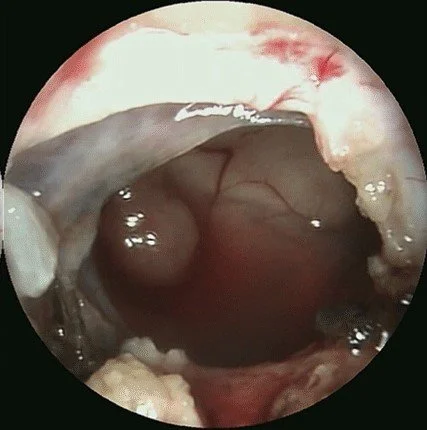

Разделителната способност на 3Д ендоскпа освен реалистичния образ позволява и по-доброто разграничаване на здравата от патологично променената част на тъканите (тумор или друга тъкан). Допълнителен специализаран софтуер може да променя образа и да го превърне в 3Д спектрoскопичен, като по този начин се постига ясно изобразяване на кръносните съдове в тъканите (нормални и патологични).

Фигура 3.а.-ендоскопски изглед и 3.б микродоплер